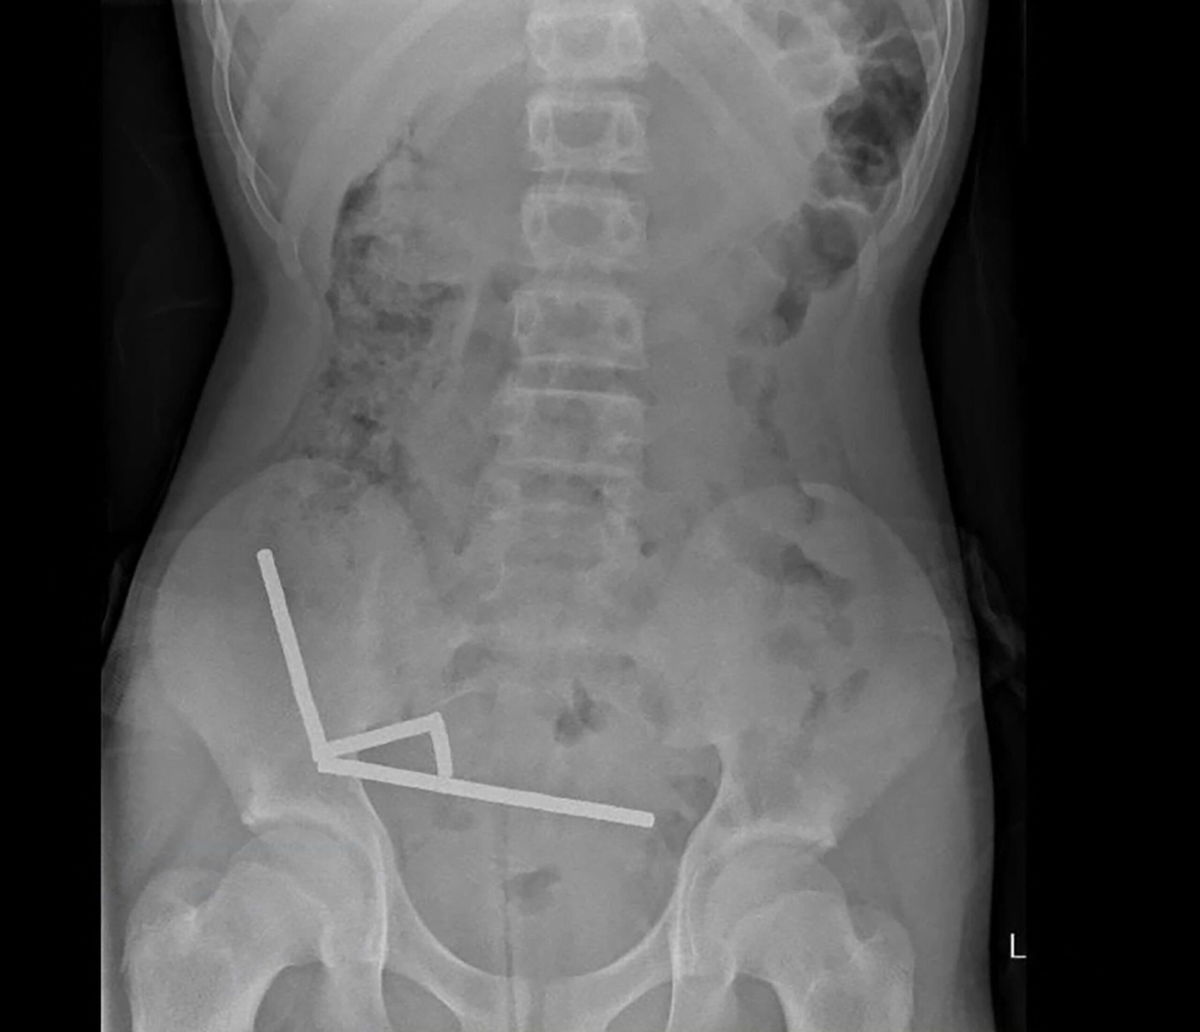

Scans revealed the magnets had clustered into four chains in the lower-right side of his abdomen, pulling together different sections of his bowel with their magnetic force, the report said, noting some imagery was distorted by the magnets. Doctors then proceeded with exploratory surgery.